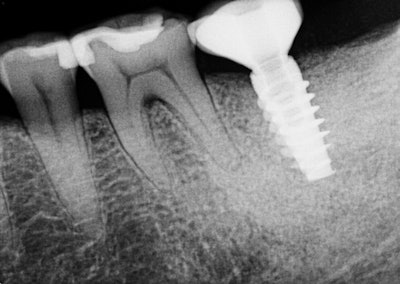

Oral exam revealed a lower left second molar tooth with class III mobility and severe occlusal wear. Periapical pathology was present because of a poorly treated root canal. A CBCT scan gave us a clear understanding that tooth #18 was hopeless and was literally floating in pathology.

Incidental findings were present: a mesiodens in the area of #9 with an associated asymptomatic periapical lesion.

This patient was a medical professional and was thankful for the level of expertise that we provided her, and she moved forward with the extraction, bone graft, implant, and restoration of tooth #18 that was necessary to return her to a full complement of teeth.